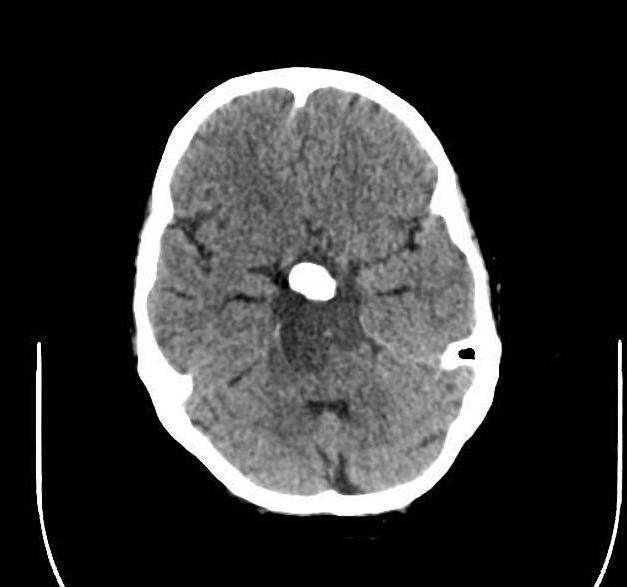

U sọ hầu

» Thông tin: Nam giới – 30 tuổi.

» Lâm sàng: Đau đầu.